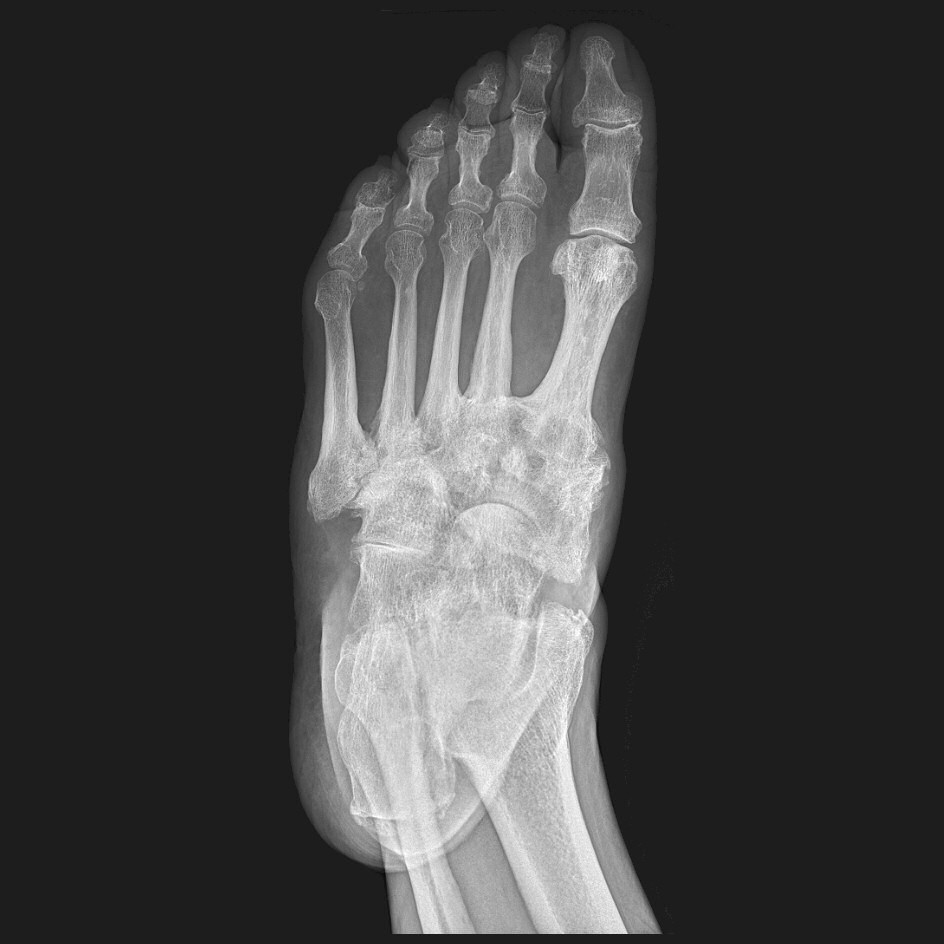

Obehandlad charcotfot, patienten noterade formförändring i fot ca 1 månad innan undersökning